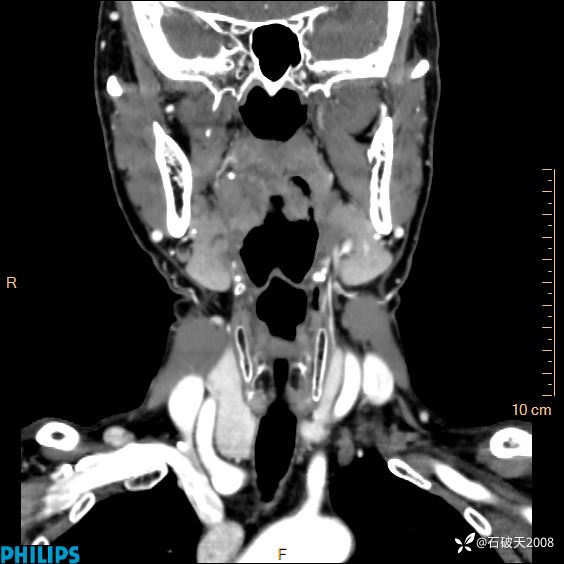

冠状位